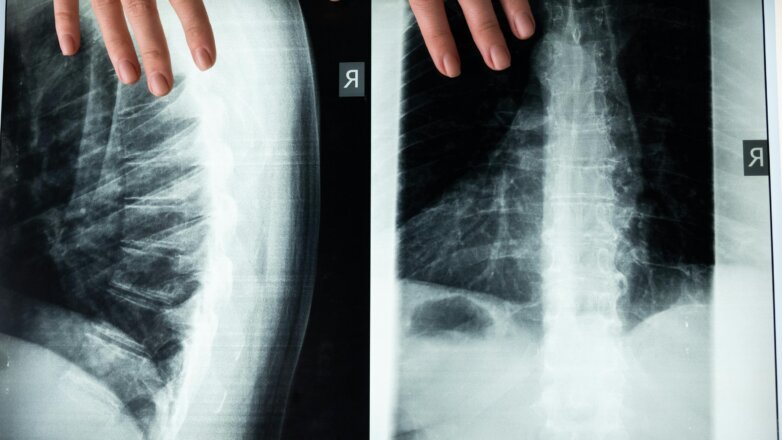

Oι γιατροί χρειάζονται περισσότερη εκπαίδευση σχετικά με την αξονική σπονδυλαρθρίτιδα